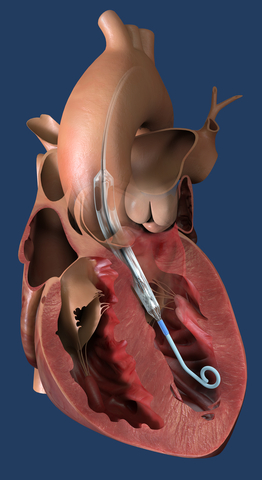

DANVERS, Mass.--(BUSINESS WIRE)--Abiomed (Nasdaq: ABMD) annuncia che la Food and Drug Administration (FDA) degli Stati Uniti ha approvato la versione di Impella ECP che verrà utilizzata nello studio clinico fondamentale su Impella ECP, e i primi due pazienti sono stati arruolati nello studio. Amir Kaki, MD, direttore del supporto meccanico al circolo presso l'Ascension St. John Hospital di Detroit, ha guidato le procedure. Questo trial prospettico, multicentrico, a braccio singolo valuterà la percentuale degli eventi maggiori cardiovascolari e cerebrovascolari (MACCE) nei pazienti adulti che ricevono il supporto Impella ECP durante un intervento coronarico percutaneo (PCI) ad alto rischio elettivo o urgente.